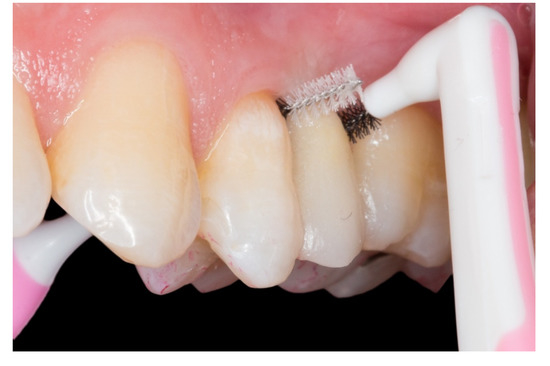

Figure 8.

The embrasures are released allowing adequate interproximal brushing, avoiding periodontal disease and interproximal caries.

On this “T” technique the embrasures are released allowing an adequate interproximal brushing, avoiding periodontal disease and interproximal caries (Figure 8).

All the cases had a clinically acceptable periodontal condition due to the embrasures and were released allowing adequate interproximal brushing. The patients reported no caries, no temperature or pressure sensitivity during the follow-up and all the abutment teeth were vital at the final examination appointments.

Regarding the periodontal aspect and the development of interproximal caries, few articles have been written on this very important aspect [2]. We consider it to be one of the main problems in this type of restoration, due to the need to build a strong and solid framework. Practitioners invade periodontal tissue, generating plaque accumulation causing chronic periodontal inflammation and the development of interproximal caries in the abutment teeth. This technique that we propose uses inlay retainers and two fiberglass pins which form the “T” structure is very solid and stable, allowing the release of embrasures and enabling adequate interproximal brushing. For this reason, as mentioned in the article by Izgi et al. [2], it is important to have follow-ups every six months in order to control the absence of complications in the FRCB and to check up on the abutment teeth. In our opinion, adequate brushing techniques, flossing properly and interproximal brushing should be taught by the practitioners to avoid complications in abutment teeth (interproximal caries and periodontal inflammation).

- The periodontal inflammation aspect on the pontic area: the framework design releases the embrasures allowing adequate interproximal brushing, avoiding periodontal disease and interproximal caries.